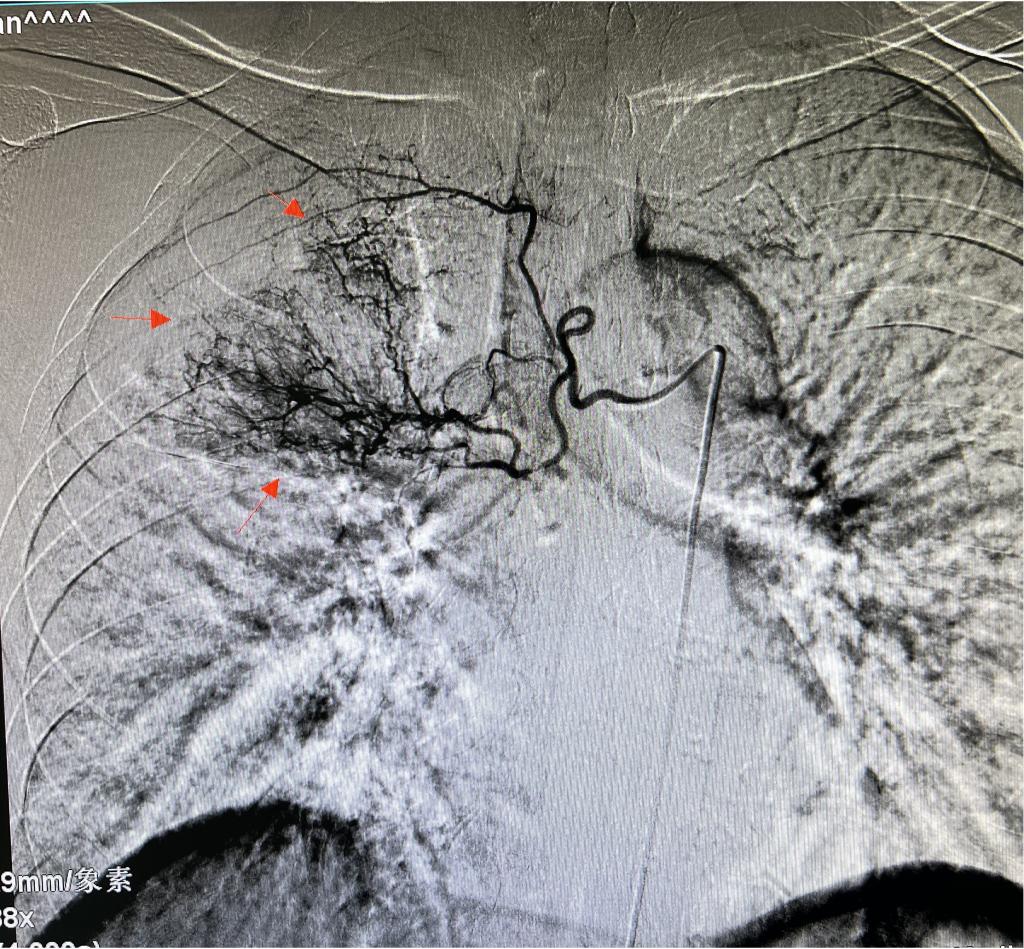

患者刘某,女性,75岁,结核咯血保守治疗十余天后突发大咯血,介入科会诊后急诊行经皮支气管动脉造影并出血动脉栓塞术。正值午饭时间,但一期二期手术室均有平诊患者,介入科主任李建国立即协调临床相关科室停止平诊手术,争分夺秒确保绿色通道危急重患者第一时间得到救治。护士长白小爱组织护理团队对术室消杀、积极术前准备。副主任何彤迅速通过支气管动脉造影确认出血动脉,历经数十分钟紧张有序的精准栓塞,原出血立止,患者转危为安。